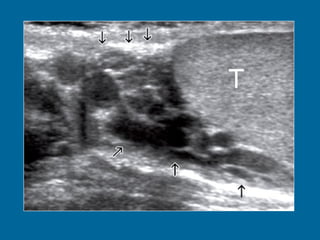

Tumor del seno endodermico mass.  (a)  Longitudinal US scan of the left hemiscrotum shows a solid tumor  (T)  replacing the entire testis. The cystic areas (arrowheads) represent tumor necrosis.

Tumor del senoendodermico mass. (a) Longitudinal US scan of the left hemiscrotum shows a solid tumor (T) replacing the entire testis. The cystic areas (arrowheads) represent tumor necrosis.